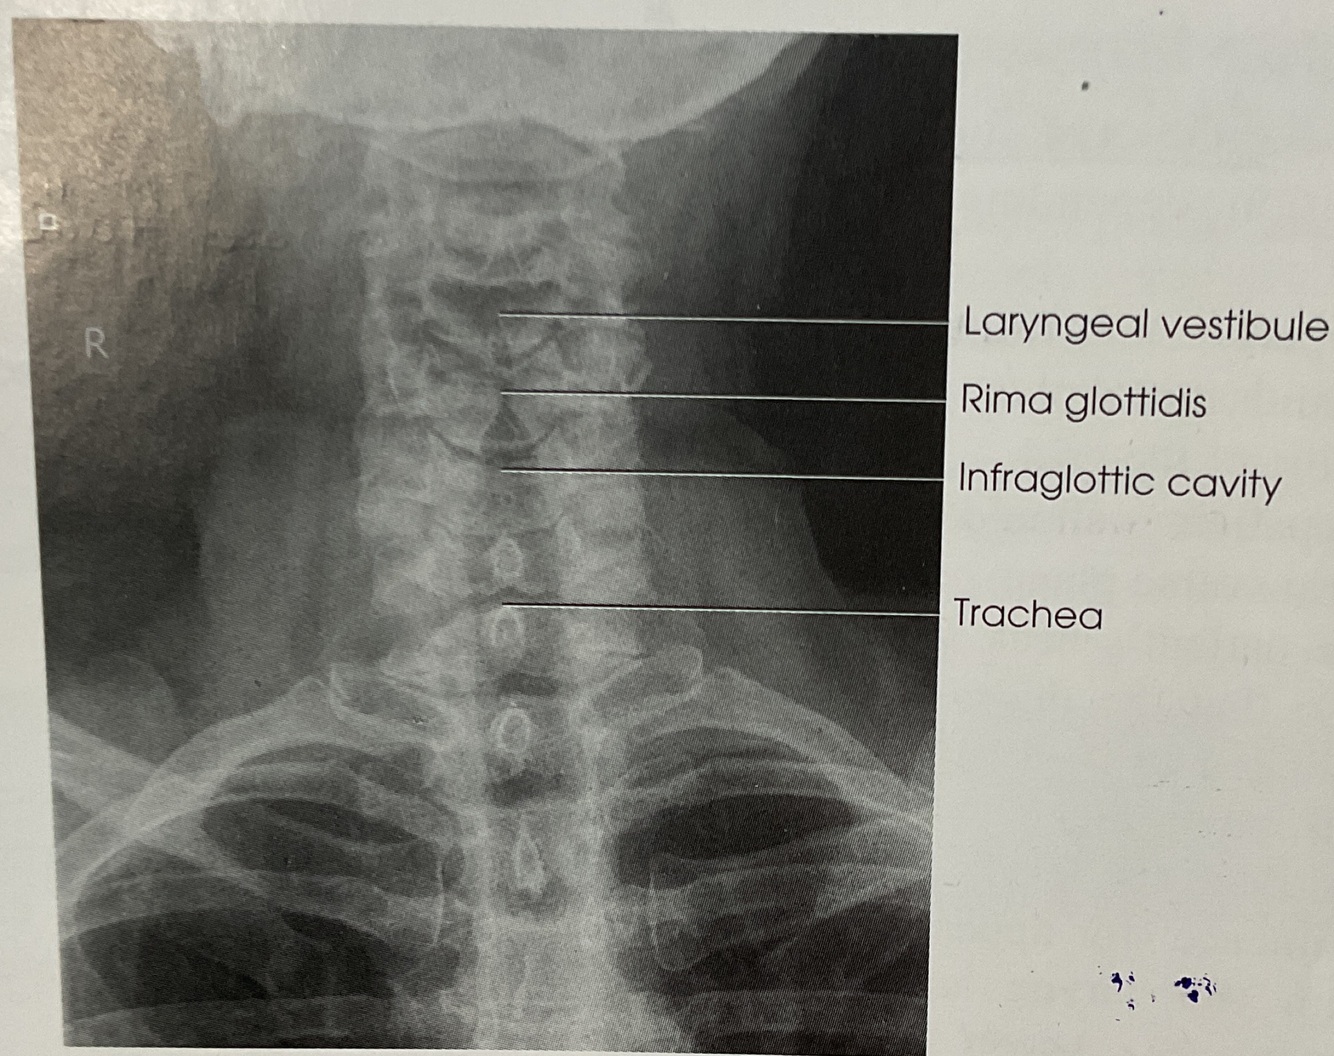

~ Air Filled Upper Airway from Pharynx to Proximal. trachea (UPPER AIRWAY)

~ AIr filled airway from midcervical to midthoracic region (TRACHEA & SUPERIOR MEDIASTINUM)